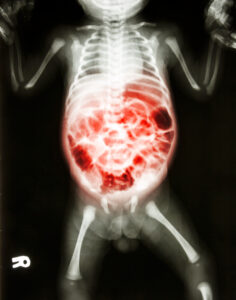

Read MoreA jury in Baltimore opted to award the Anne Arundel County family nearly $35 million dollars in a recent judgment. Learn more about this case that ended with the disability of an infant child.

Read MoreHow do you tell if an NEC case constitutes negligence or malpractice becomes a crucial consideration? Here is everything you need to know.